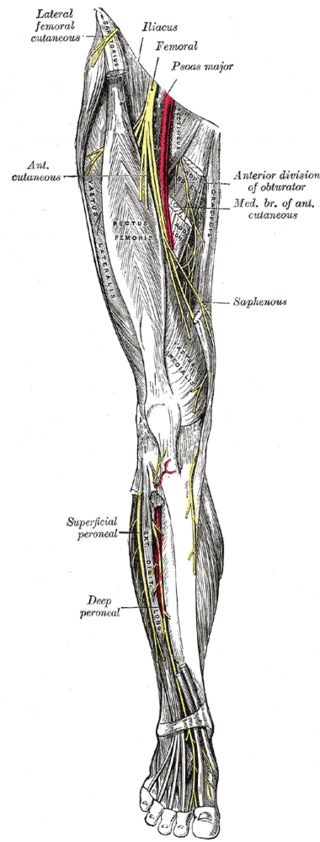

앞무릎 전체 통증: 대퇴신경 포착(Femoral nerve entrapment)

앞무릎 전체 통증: 대퇴신경포착(Femoral nerve entrapment)

아픈 부위를 가르켜 보라고 하면 정확한 부위를 가르키지 못하고 전체가 다 아프다고 하시는 분들이 있습니다. 임상 경험상 이런 경우는 대퇴신경의 포착이거나 중추신경의 과민화로 인한 요추 2,3,4번 레벨의 연관통으로 보여집니다.

처음 시작은 무릎 통증이었으나 오랜 시간 낫지 않고 반복적인 무리를 하면 전체적으로 다 아프다고 느끼게 됩니다. 이런 경우 대퇴신경의 척추레벨인 요추2,3,4번 다열근의 압통점을 확인하여 먼저 치료하게 됩니다. 그러면 최초 시작한 부위의 통증으로만 남게 되는 경우가 많죠. 또는 대요근에 의해 대퇴신경이 포착될 수 있습니다. 대퇴신경이 지배하는 대퇴사두근의 허혈성 통증이 나타나고 무릎 전체적으로 통증을 느끼게 됩니다.